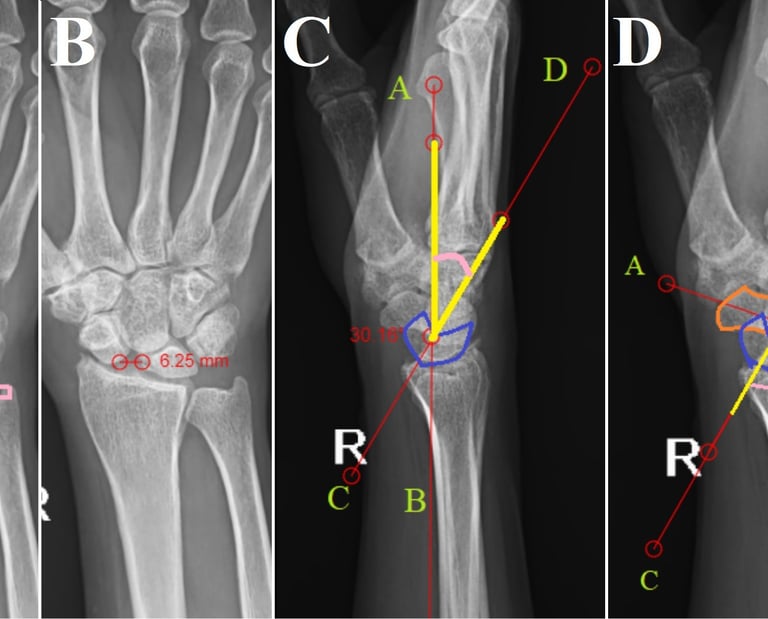

Scapholunate Advanced Collapse Wrist - Keeping it Simple

Scapholunate advanced collapse is a rare condition of progressive deformity, instability, and arthritis that affects the radiocarpal and mid-carpal joints of the wrist. It occurs as a result of injury to the scapholunate ligament being left untreated. A complete in-depth radiological analysis can demonstrate several signs that can prevent missed diagnosis. Increased awareness regarding these radiological signs can avoid the unnecessary higher imaging modalities being performed.

Isolated lunate dislocation

Perilunate dislocations are rare traumatic injuries of the wrist. They are classified according to the Mayfield classification system. Among these, lunate dislocations represent only the type IV injury, which are among the most unstable. Isolated lunate dislocations are often unrecognised as the rest of the carpus remains aligned. The rate of incorrect diagnosis is reported to be as high as 25%. Neglected lunate dislocations can lead to median nerve dysfunction, carpal instability, avascular necrosis of lunate and arthritis. Careful analysis of radiographs is required for diagnosis, indicated by disruptions of Gilula’s arc, lunocapitate overlap on posteroanterior radiographs and spilling teacup sign, increased radiolunate angle on lateral radiographs.